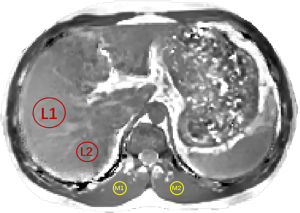

Liver magnetic susceptibility, R2*, and PDFF values were measured using region of interest (ROI) analysis. ROIs were manually drawn on the QSM images using ITK-SNAP software (version 3.8.0, www.itksnap.org) by the two radiologists mentioned above who were blinded to the clinical history, blood markers data, and liver biopsy results. First, through consensus, both reviewers determined the single liver slice which contained an as-large-as-possible cross section through the liver and the least motion artifacts to measure. Then, ROIs ranging from 5 to 8 cm2 were independently placed in this consensus slice in the anterior and posterior segment of the right lobe of the liver where a biopsy specimen was obtained (Figure 3). The other two ROIs ranging from 1.8 to 3.6 cm2 in the same slice were placed in the latissimus dorsi muscle on either side of the spine as a reference for determining the relative susceptibility in the hepatic parenchyma, as the latissimus dorsi muscle does not accumulate iron (28,33). All ROIs were drawn in the area in which the signal was as homogeneous as possible, and large blood vessels and cavities were avoided. ROIs in the liver were at least 7.2 mm away from the air boundary, while ROIs in the latissimus dorsi muscle were 3.6–7.2 mm away from the tissue border and the air boundary. The ROIs were then copied to corresponding R2* and PDFF images for measurements. R2* and PDFF values were measured and averaged on the liver ROIs, while the relative value between the averaged values on the liver ROIs and on the latissimus dorsi muscle ROIs was calculated as the hepatic susceptibility value. To evaluate the reproducibility of the ROI sampling, the above ROI drawing and analyses were repeated by both radiologists after 4 months.